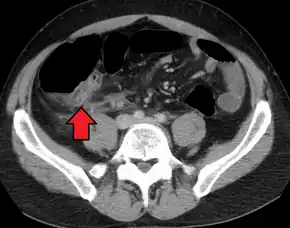

In children, the clinical examination is important to determine which children with abdominal pain should receive immediate surgical consultation and which should receive diagnostic imaging.[50] Because of the health risks of exposing children to radiation, ultrasound is the preferred first choice with CT scan being a legitimate follow-up if the ultrasound is inconclusive.[51][52][53] CT scan is more accurate than ultrasound for the diagnosis of appendicitis in adults and adolescents. CT scan has a sensitivity of 94%, specificity of 95%. Ultrasonography had an overall sensitivity of 86%, a specificity of 81%.[54]

Computed tomography

Where it is readily available, computed tomography (CT) has become frequently used, especially in people whose diagnosis is not obvious on history and physical examination. Although some concerns about interpretation are identified, a 2019 Cochrane review found that sensitivity and specificity of CT for the diagnosis of acute appendicitis in adults was high.[59] Concerns about radiation tend to limit use of CT in pregnant women and children, especially with the increasingly widespread usage of MRI.[60][61]

The accurate diagnosis of appendicitis is multi-tiered, with the size of the appendix having the strongest positive predictive value, while indirect features can either increase or decrease sensitivity and specificity. A size of over 6 mm is both 95% sensitive and specific for appendicitis.[62]

However, because the appendix can be filled with fecal material, causing intraluminal distention, this criterion has shown limited utility in more recent meta-analyses.[63] This is as opposed to ultrasound, in which the wall of the appendix can be more easily distinguished from intraluminal feces. In such scenarios, ancillary features such as increased wall enhancement as compared to adjacent bowel and inflammation of the surrounding fat, or fat stranding, can be supportive of the diagnosis. However, their absence does not preclude it. In severe cases with perforation, an adjacent phlegmon or abscess can be seen. Dense fluid layering in the pelvis can also result, related to either pus or enteric spillage. When patients are thin or younger, the relative absence of fat can make the appendix and surrounding fat stranding difficult to see.[63]